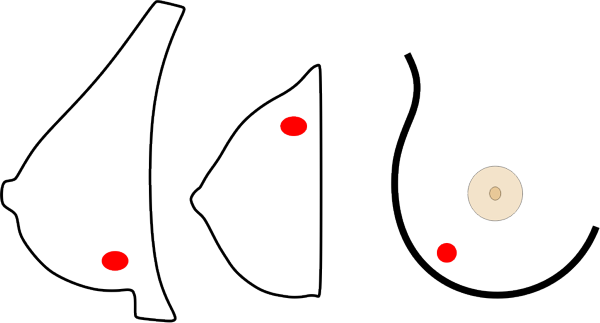

Von jeder Brust werden üblicherweise zwei Aufnahmen - jeweils von oben nach unten (cranio-caudale Aufnahme) und schräg von innen nach außen (medio-laterale oblique Aufnahme) - angefertigt. Die Brust wird dabei in eine Vorrichtung eingespannt und komprimiert:

Die cc-Aufnahme wird immer so dargestellt, dass die Außenseite der Brust im Bild oben liegt.

können die Brustabschnitte in der Nähe der Achsel besser dargestellt werden.

Die Brust ist ein dreidimensionales Organ, die Aufnahmen sind hingegen flach. Um die sichtbaren Strukturen räumlich richtig einordnen zu können, sind daher zwei Aufnahmen in verschiedenen Ebenen notwendig.